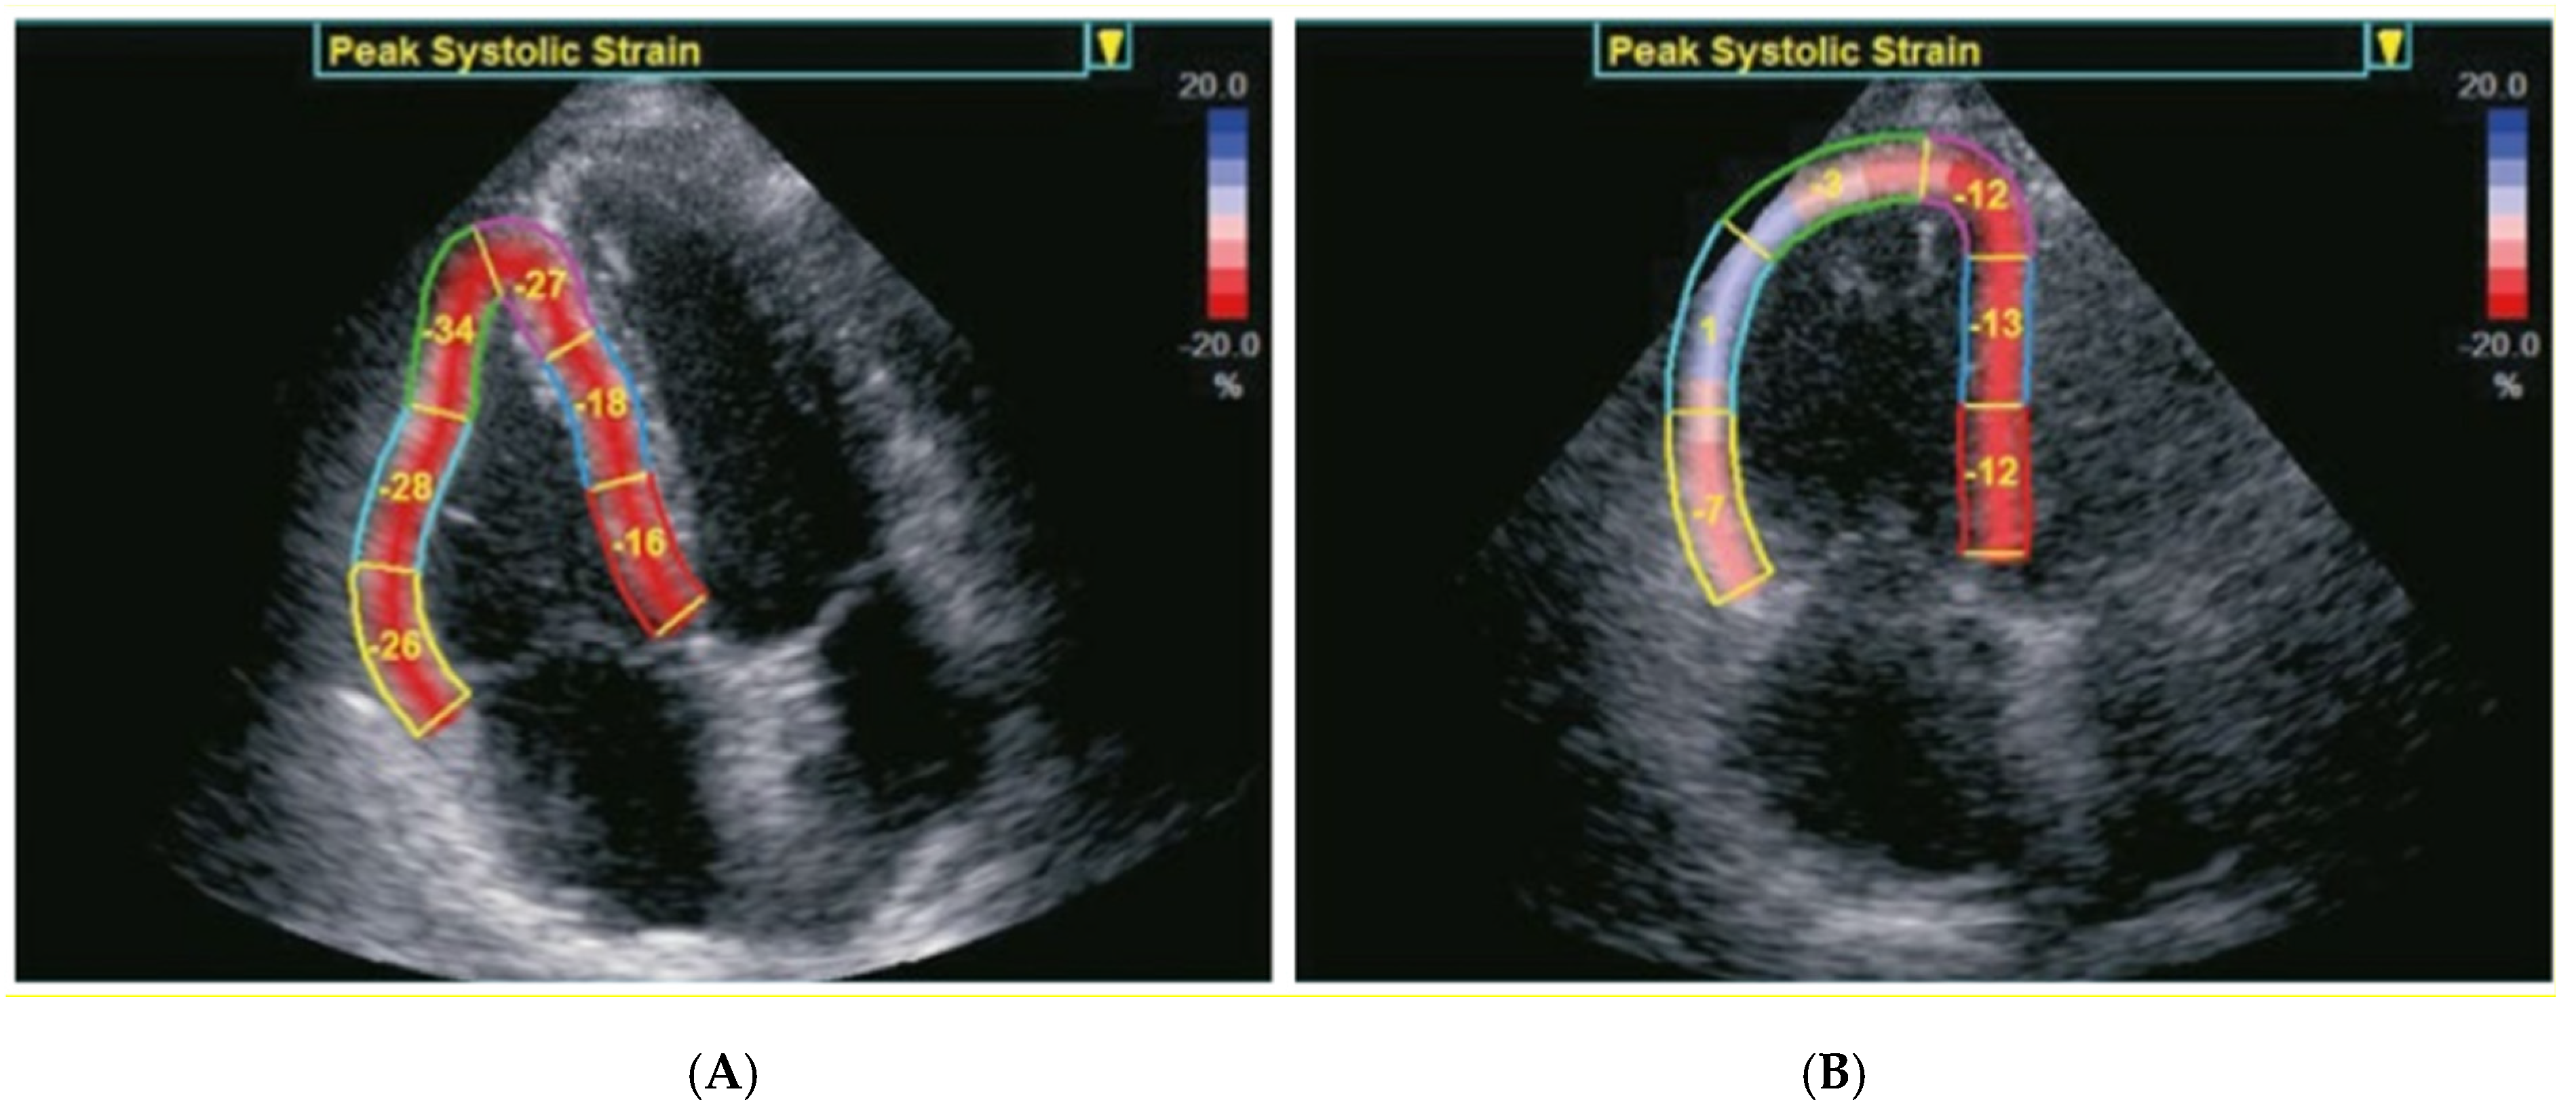

| RV basal wall LS (%) | −21.5 ± 7.9 | −20.8 ± 8.3 | 0.25 |

| RV middle wall LS (%) | −21.5 ± 8.2 | −21.1 ± 8.3 | 0.52 |

| RV apical wall LS (%) | −15.7 ± 8.4 | −17.1 ± 7.9 | 0.04 |

| Average RV free−wall LS (%) | −20.0 ± 7.6 | −19.8 ± 7.8 | 0.7 |